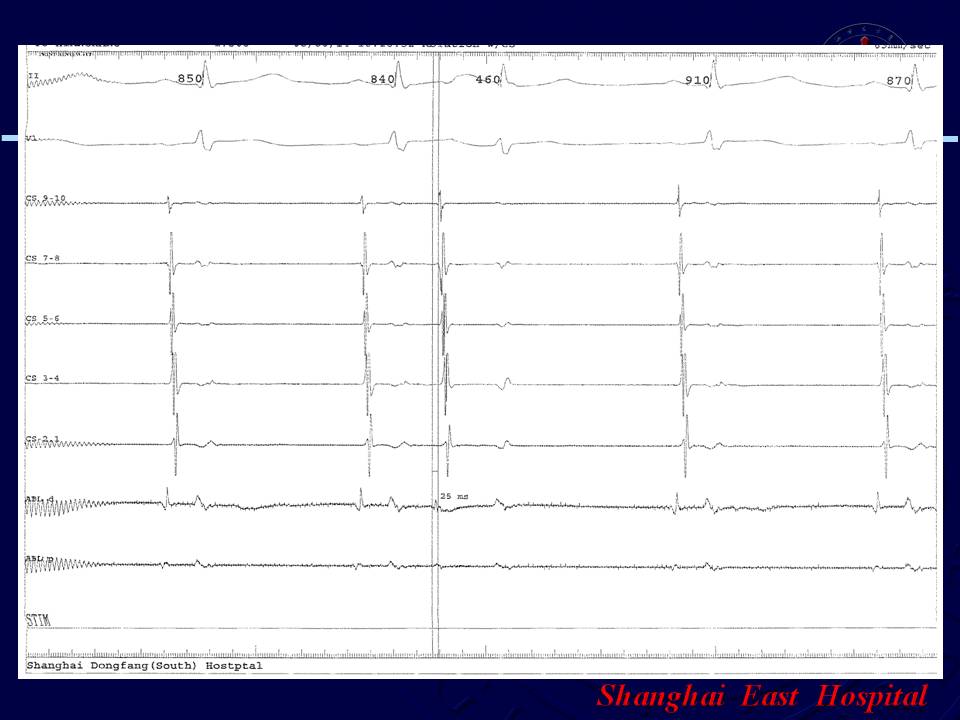

阵发性房颤、无冠窦房早射频消融1例

谭红伟 张旭敏 邹誉 周建 刘学波